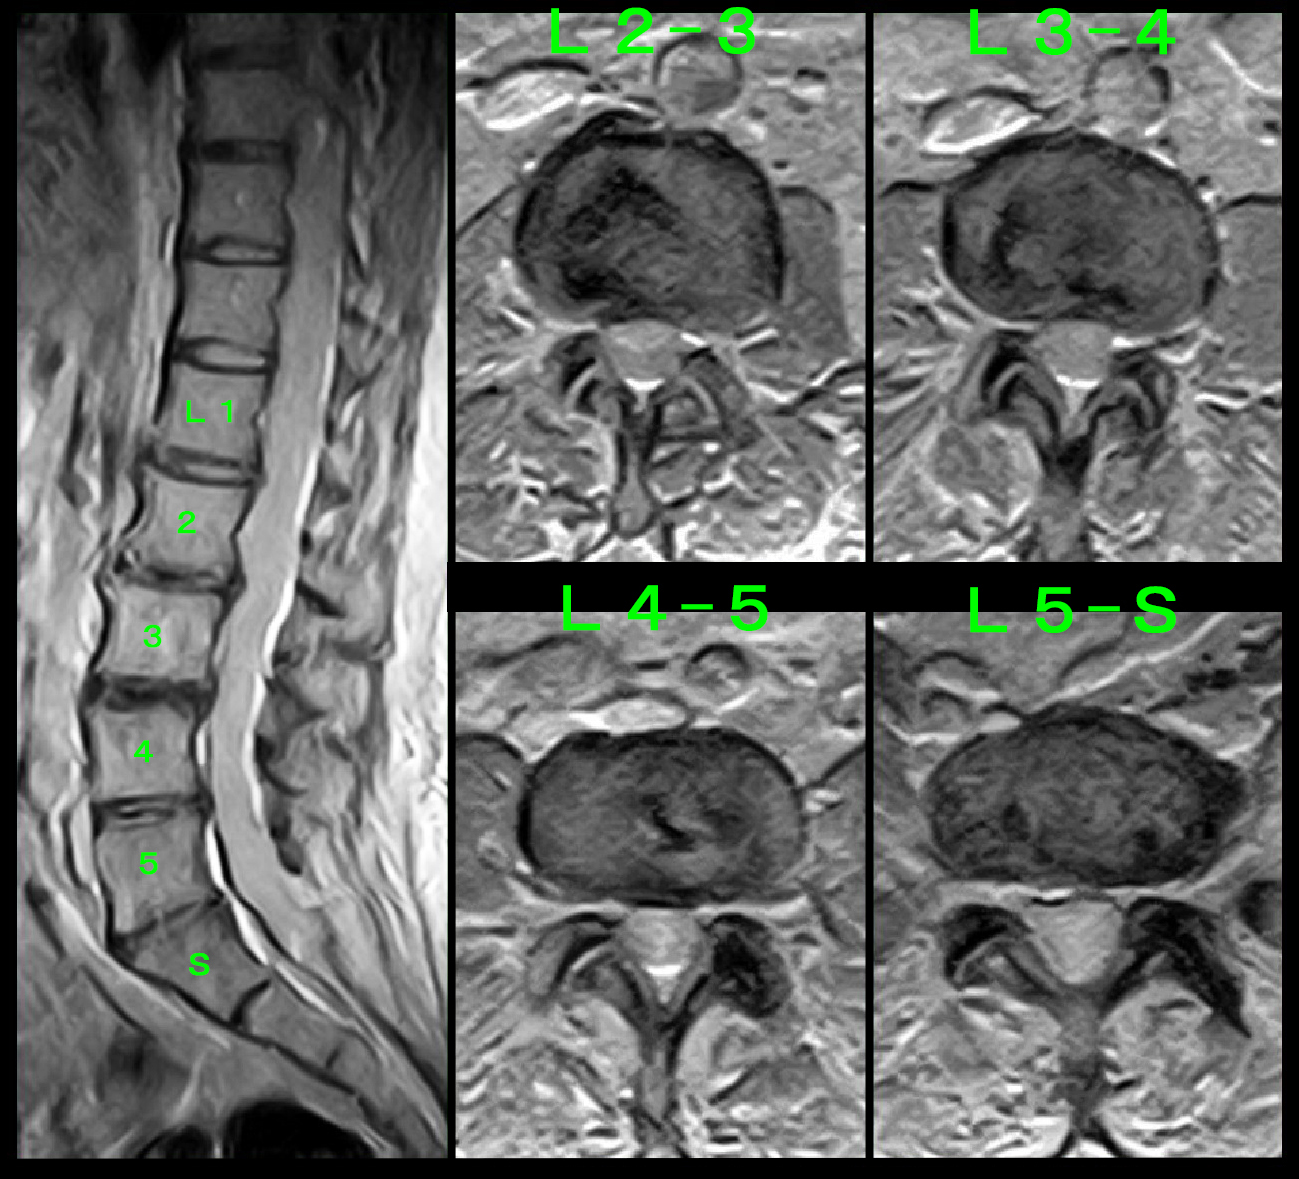

70才女 就眠時MR.jpg

MRI検査では全体としては軽度の腰部脊柱管狭窄症の所見ですが、私の経験的判断ではL45高位は中等度の脊柱管狭窄の所見と評価されて、これに起因する腰痛・右臀部痛と診断し、右L5神経根ブロックを施行しました。